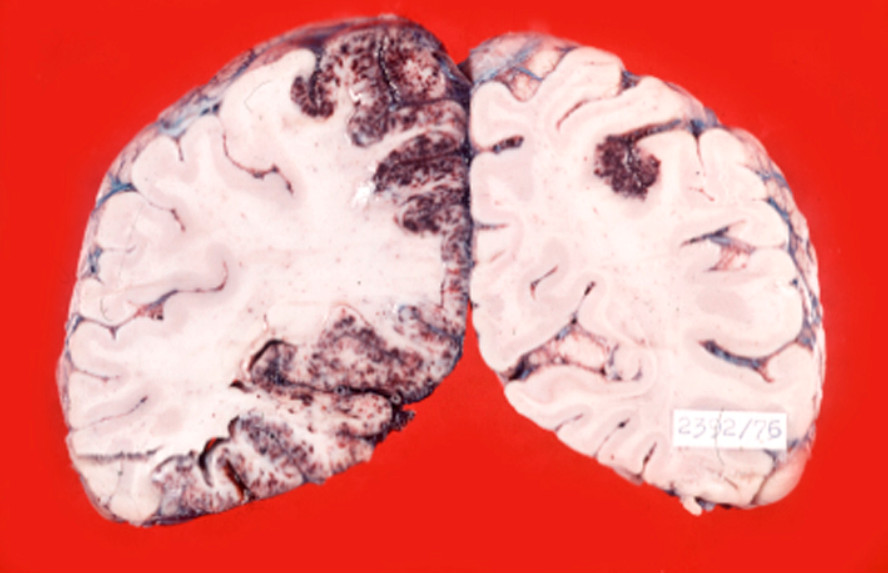

Zawał krwotoczny, w którym poza obrzękiem istoty szarej i białej dochodzi do przesiękania krwi przez uszkodzone ściany naczyń krwionośnych, powodując tzw. „nadziankę krwawą” z licznymi wybroczynami, występuje głównie w: